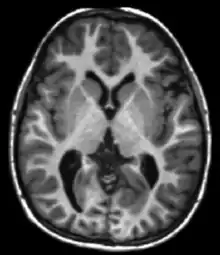

) of those nuclei after the pulse sequence, and often on other parameters discussed under specialized MR scans. Contrast in most MR images is actually a mixture of all these effects, but careful design of the imaging pulse sequence allows one contrast mechanism to be emphasized while the others are minimized. The ability to choose different contrast mechanisms gives MRI tremendous flexibility. In the brain, T1-weighting causes the nerve connections of white matter to appear white, and the congregations of neurons of gray matter to appear gray, while cerebrospinal fluid (CSF) appears dark. The contrast of white matter, gray matter and cerebrospinal fluid is reversed using T2 or T*

2

imaging, whereas proton-density-weighted imaging provides little contrast in healthy subjects. Additionally, functional parameters such as cerebral blood flow (CBF), cerebral blood volume (CBV) or blood oxygenation can affect T1, T2, and T*

and so can be encoded with suitable pulse sequences.